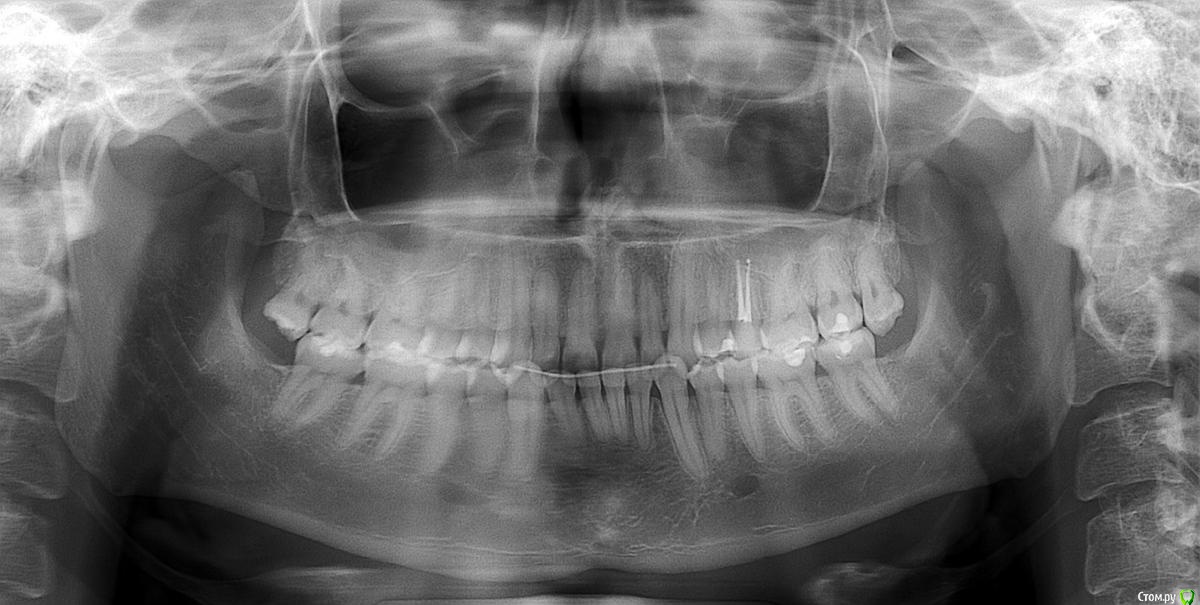

Добрый день! Я проходил лечение брекет системой (2010- 2014г.г.) В то время я не был осведомлен об эстетических результатах при неправильном подходе к лечению. Результат теперь можно наблюдать на приложенных изображениях. Уменьшилась нижняя треть лица, нарушились пропорции. Здесь не так видно, но челюсть приобрела совсем уж небольшие размеры и как бы имеет задвинутое положение. Занять привычное положение ей мешает передний наклон нижних резцов. Посоветуйте, в чем причина (в ретропозиции ВЧ, в НЧ, в еще чем) и как ее решать?  (Ортодонтия, Ортопедия или все таки хирургия)?

Томограмма после http://pixs.ru/showimage/2016060314_8022204_22193232.jpg